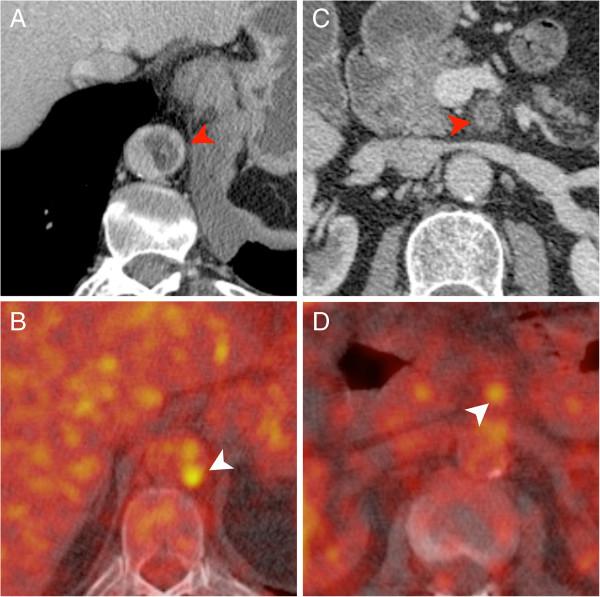

The median interval between the first imaging study and the final diagnosis was 11 weeks (0-12 weeks). The most frequently observed imaging findings suggestive of malignant disease in patients with sarcomas of the pulmonary arteries were a large filling defect with vascular distension, unilaterality and a lack of improvement despite effective anticoagulation. In patients with aortic sarcomas we most frequently observed a pedunculated appearance and an atypical location of the filling defect. The F-18 FDG PET(/CT) examinations demonstrated an unequivocal hypermetabolism of the lesion in all cases (4/4). MRI proved lesion vascularization in 5/6 cases.

首次影像检查与最终诊断的中位间隔时间为11周(0 - 12周)。肺动脉肉瘤患者中最常观察到的提示恶性疾病的影像表现为伴有血管扩张的大充盈缺损、单侧性以及尽管进行了有效的抗凝治疗但仍无改善。在主动脉肉瘤患者中,我们最常观察到带蒂外观和充盈缺损的非典型位置。F-18 FDG PET(/CT)检查在所有病例(4/4)中均显示病变明确的高代谢。MRI在5/6例病例中证实了病变的血管化。